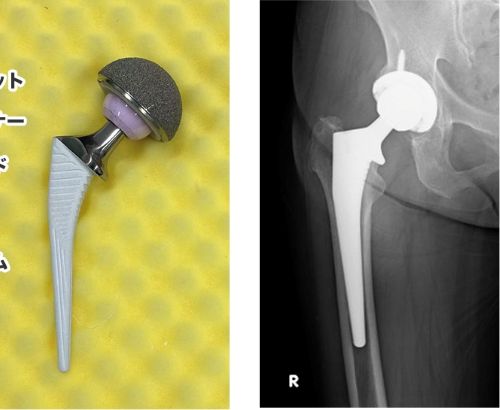

股関節を人工関節に置換する手術を受けてから、一年が経ちました。昨日、一年検診を受けたところ、レントゲンでも経過は良好、医師からも「まったく問題ありません」とのお墨付きをいただきました。素直に嬉しく、安心しています。そもそも手術に至った原因は、「ダイエットのため」に始めた早朝ランニングでした。10年前に禁煙した私は、体重管理の一環として、毎朝走る習慣を続けてきました。しかし約5年前、歩道の縁石につまずいて転倒した際、左足をかばうようなフォームになってしまったようです。それが股関節の痛みに繋がり、整形外科で「左の股関節の軟骨が完全に擦り減っている」と診断されました。最初の治療法として、中殿筋を鍛える運動を勧められました。中殿筋は、歩行や片足立ちの際に骨盤を安定させる重要な筋肉です。私はすぐに毎日のゴムチューブ運動を始め、1年半続けました。確かに筋力はつきましたが、それでも痛みは完全には引かず、親戚のドクターのアドバイスも有り、ついに昨年手術を決断しました。術後は日に日に回復。当初17日間を見込んでいた入院期間は、わずか8日で退院できるまでに回復しました。これは間違いなく、継続してランニングやゴムチューブで鍛えてきた成果だったと思います。ただ、今回の経験で感じたのは、「やりすぎは、時に逆効果になる」ということ。健康とダイエットを意識して始めたランニングも、やり方を誤れば、かえって身体を痛めることに繋がります。運動も、努力も、何事も「ちょうどよい加減」がある。「過ぎたるは猶及ばざるが如し」――身をもって学んだ言葉です。これからは、無理せず、でも怠らず、自分の身体と相談しながら毎日トレーニングしていきたいと思います。